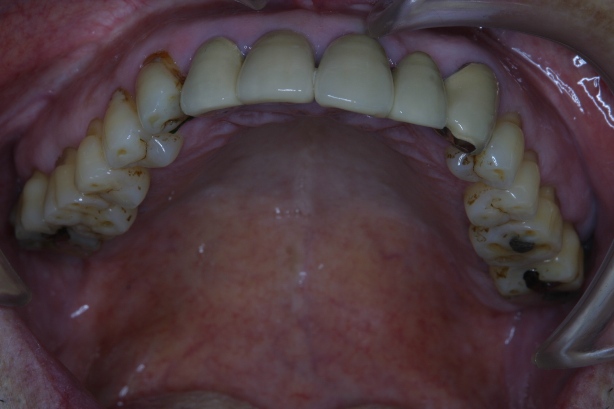

「8020運動」 表彰に出て頂いた方々のお口を拝見